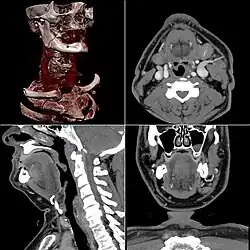

КТ-ангиография

КТ-ангиография позволяет получить послойную серию изображений кровеносных сосудов; на основе полученных данных посредством компьютерной постобработки с 3D-реконструкцией строится трёхмерная модель кровеносной системы.

Спиральная КТ-ангиография — одно из последних достижений рентгеновской компьютерной томографии. Исследование проводится в амбулаторных условиях. В локтевую вену вводится йодсодержащий контрастный препарат в объёме около 100 мл. В момент введения контрастного вещества делают серию сканирований исследуемого участка.